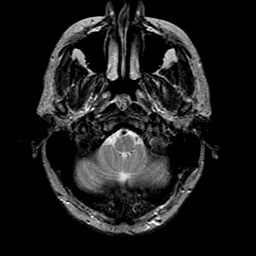

glioma overlay -- Slice #3

[Home][Help][Clinical] Slice 3